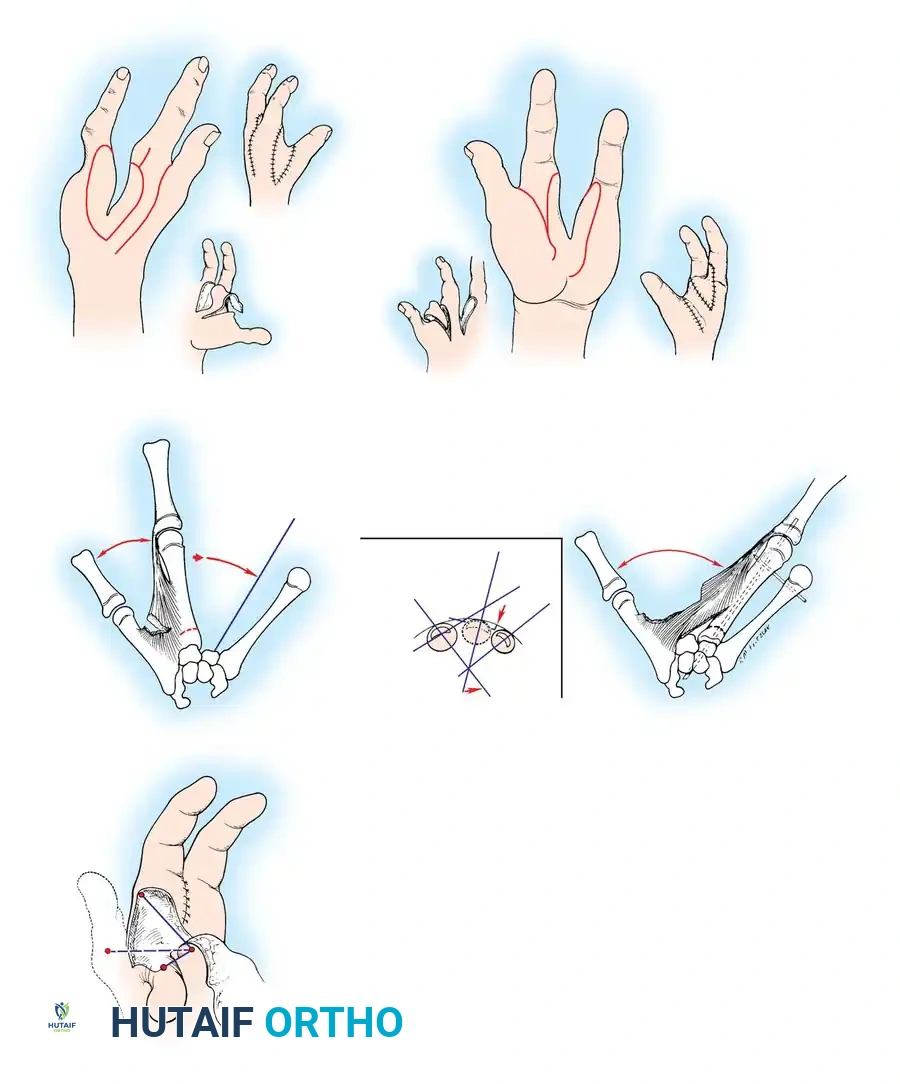

Associated Surgical & Radiographic Imaging